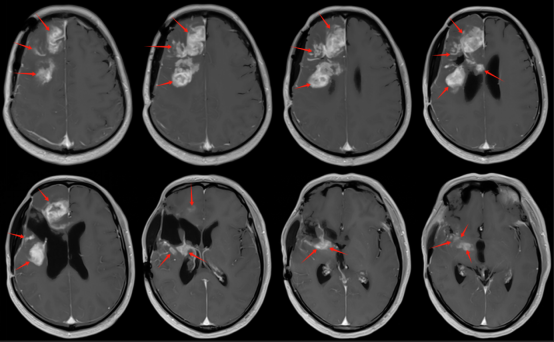

經(jīng)過(guò)2個(gè)月的治療,患者未發(fā)生癲癇,左側(cè)肢體活動(dòng)較前明顯恢復(fù),可以行走。治療中無(wú)嚴(yán)重不良反應(yīng)發(fā)生。復(fù)查頭部磁共振顯示,病灶得到良好控制,病灶大部分已縮退。剩余殘留病灶將隨后續(xù)治療,進(jìn)一步縮退。

治療前后病灶圖像對(duì)比

圖注:復(fù)查頭部磁共振,可見(jiàn)病灶基本完全控制。上排為治療前T1增強(qiáng)掃描,強(qiáng)化高亮的為腫瘤病灶。下排為治療后,可見(jiàn)病灶基本完全消退。